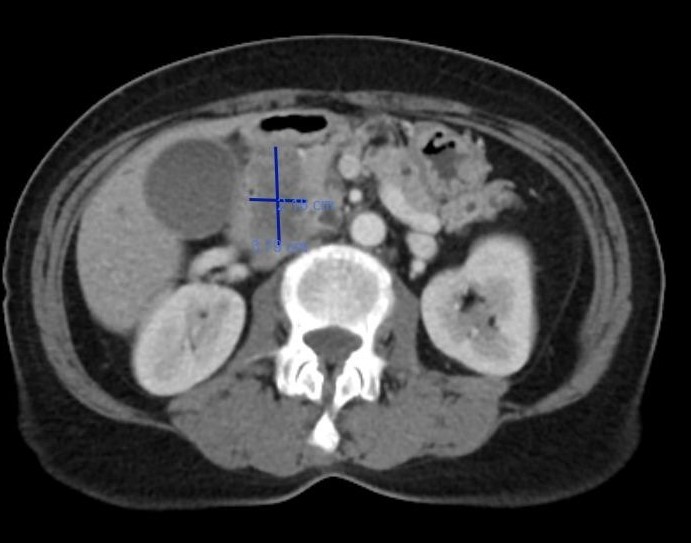

這次的主訴是腹、腰和背痛,合併頭暈嘔吐,在急診vital sign穩定,PE也沒有specific finding(包括abdominal tenderness, rebounding pain等),抽血看到TG 8000多、lipase 1000出頭。在急診的第三天休克,發燒和心跳快,當時使用了levophed等升壓藥並切了CT,看到grade E, CTSI 6的acute pancreatitis,隨後住進加護病房進行處置。